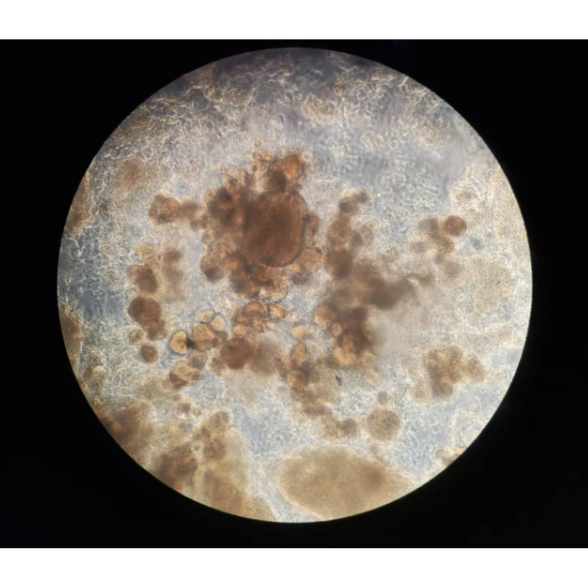

Cellspace-3D系統(tǒng)的核心在于其獨(dú)特的微重力模擬技術(shù)。該系統(tǒng)通過二軸回轉(zhuǎn)式重力模擬裝置,使培養(yǎng)容器在三維空間中進(jìn)行動(dòng)態(tài)旋轉(zhuǎn),分散重力矢量至接近零值,模擬太空“自由落體”環(huán)境。例如,系統(tǒng)通過雙軸獨(dú)立控制旋轉(zhuǎn),實(shí)現(xiàn)持續(xù)10?3g的微重力環(huán)境,與國(guó)際空間站實(shí)際微重力水平高度一致。這種設(shè)計(jì)消除了重力主導(dǎo)的細(xì)胞沉降效應(yīng),使細(xì)胞在懸浮狀態(tài)下通過黏附分子(如E-鈣黏蛋白)自發(fā)聚集,形成直徑可達(dá)500μm的三維球體或類器官。

在微重力環(huán)境下,細(xì)胞形成的三維球體內(nèi)部呈現(xiàn)梯度氧分壓、代謝物濃度及細(xì)胞外基質(zhì)(ECM)沉積,更接近體內(nèi)組織微環(huán)境。例如,肝類器官在Cellspace-3D中可形成功能分區(qū),白蛋白分泌量較二維培養(yǎng)提升3倍,CYP450酶活性提高50%,顯著增強(qiáng)藥物代謝研究的相關(guān)性。

腫瘤類器官在微重力下形成異質(zhì)性結(jié)構(gòu)(壞死核心與增殖外層),耐藥性顯著高于二維培養(yǎng)。例如,乳腺癌模型中,微重力環(huán)境使腫瘤細(xì)胞對(duì)化療藥物的耐藥性提升3倍,與上皮-間質(zhì)轉(zhuǎn)化(EMT)標(biāo)志物表達(dá)上調(diào)相關(guān),為精準(zhǔn)預(yù)測(cè)臨床療效提供關(guān)鍵數(shù)據(jù)。此外,系統(tǒng)結(jié)合微流控芯片技術(shù),可實(shí)現(xiàn)單芯片支持>100個(gè)類器官的并行評(píng)估,將藥物篩選周期從數(shù)月縮短至數(shù)周。